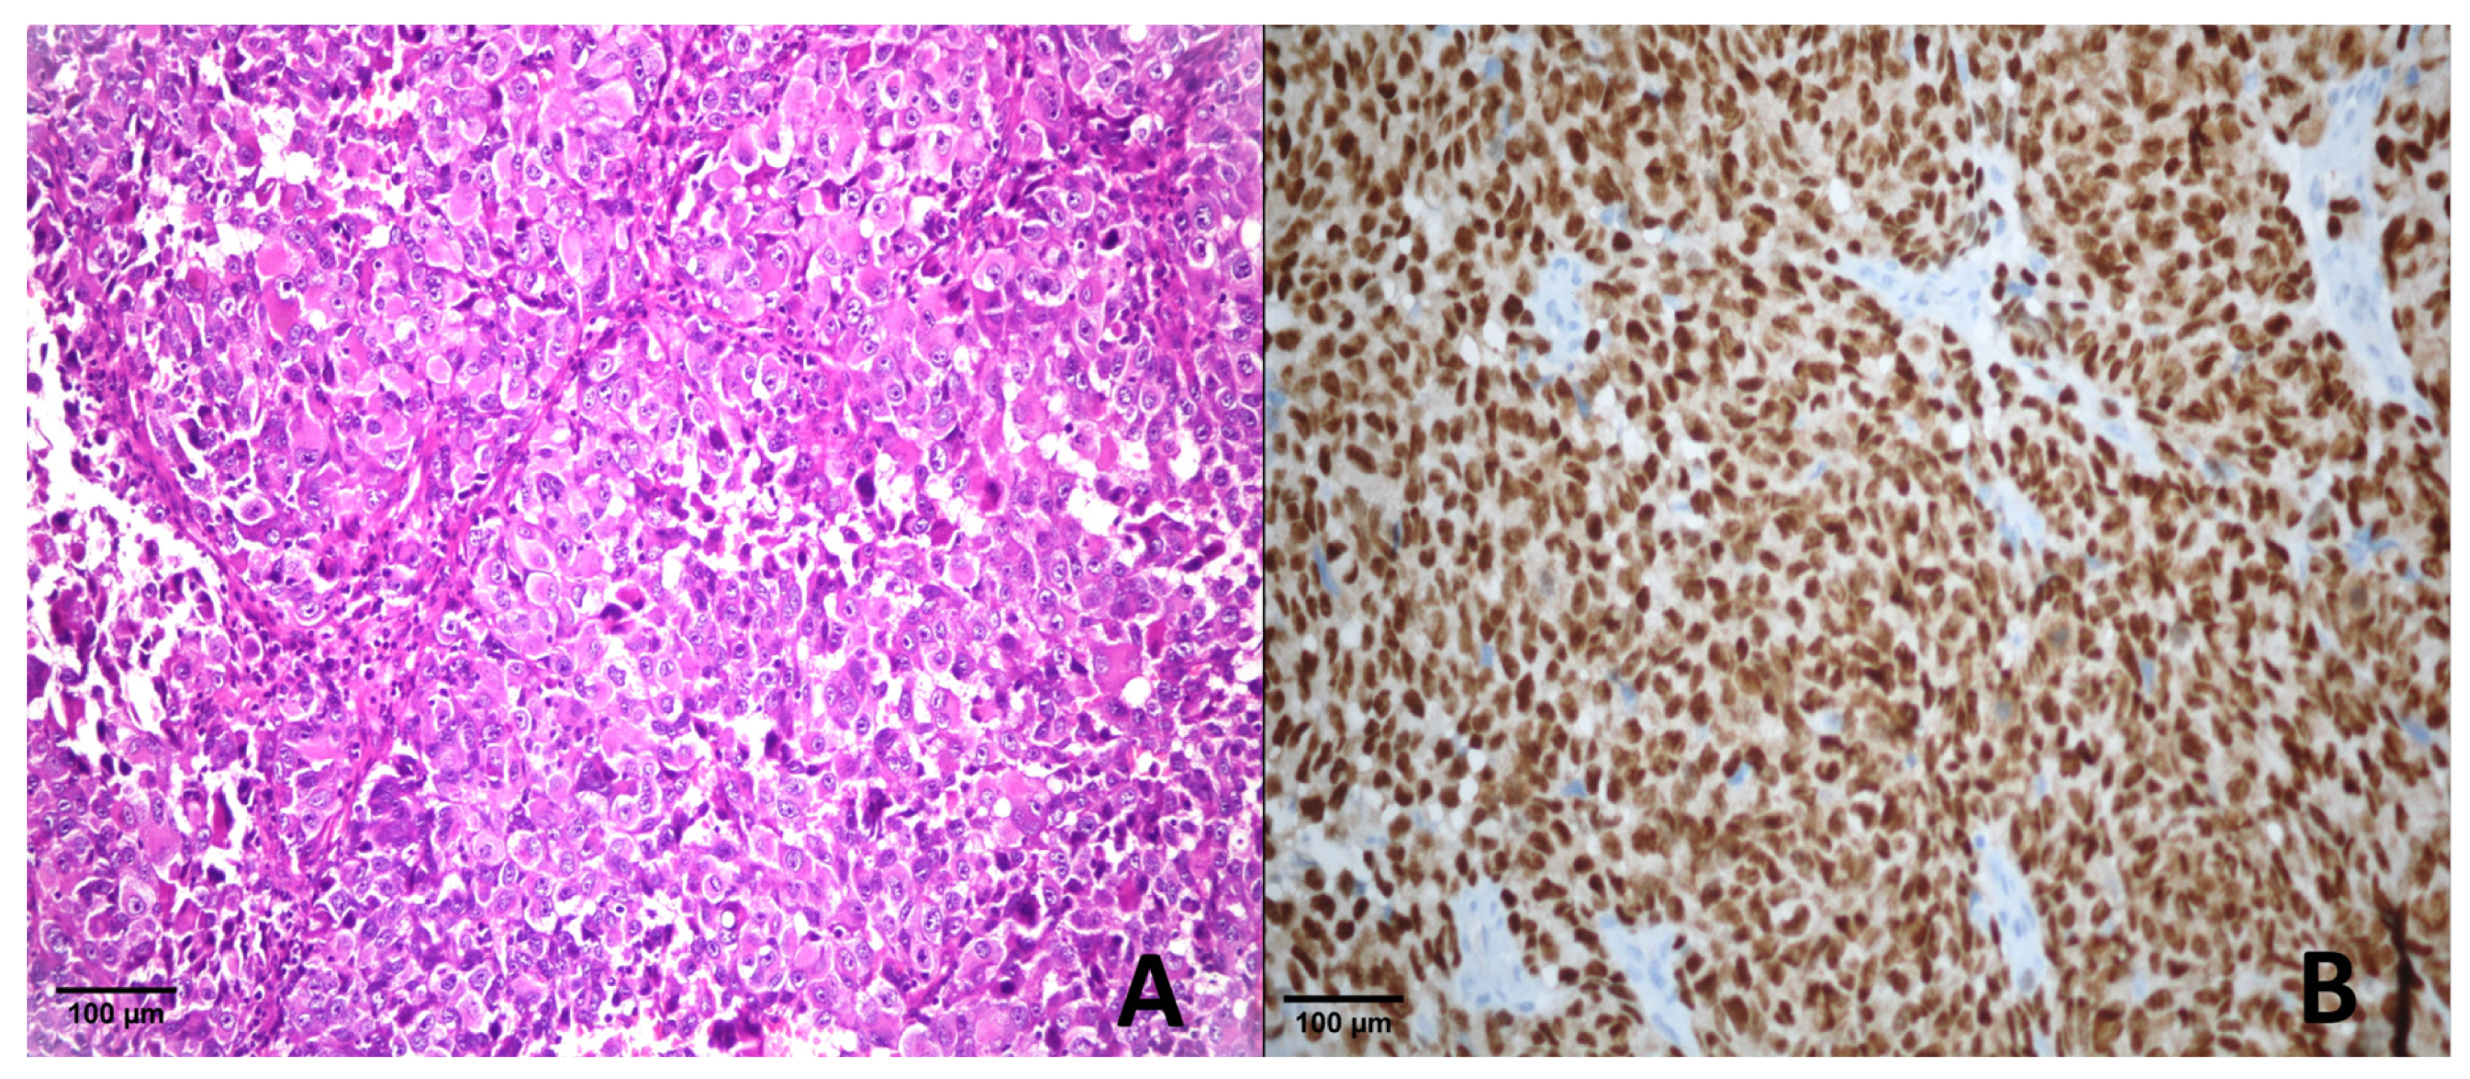

4.4.1. Metastatic Melanoma